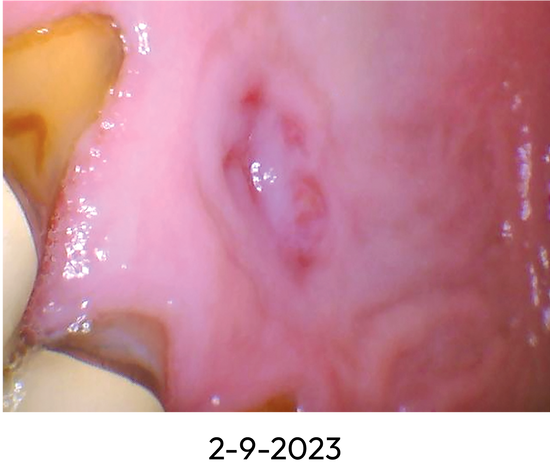

Healing Progression of Oral Lesion with Benova® Mouth Rinse System

Patient PB with diabetes, age 70.

- Patient had painful lesion for several months with no healing.

- Reported pain resolved almost immediately upon using Benova® Mouth Rinse System.